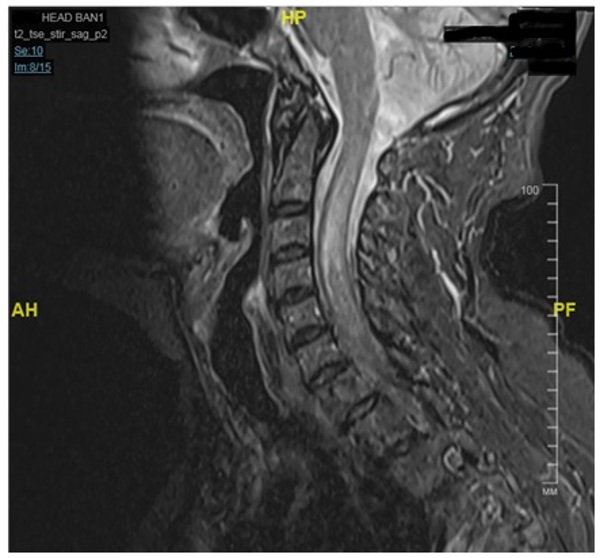

На МРТ с контрастом выявлена интрамедуллярная опухоль на уровне С4-Th1 c признаками отека спинного мозга . Пациентка была переведена в отделение нейрохирургии , выполнена операция - Микрохирургическое удаление интрамедуллярной опухоли.